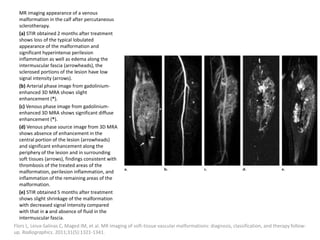

can then be treated with the sclerosant.

Müller-Wille R, Wildgruber M, Sadick M, Wohlgemuth WA. Vascular Anomalies (Part II): Interventional Therapy of Peripheral Vascular

Malformations [published online ahead of print, 2018 Feb 7]. Gefäßanomalien (Teil II): Interventionelle Therapie von peripheren

Gefäßmalformationen [published online ahead of print, 2018 Feb 7]. Rofo. 2018;10.1055/s-0044-101266.

Post-procedural care

Strict postoperative observation of the upper

airway is recommended after treatment of

patients with large cervical LMs.

Fever after injection of Picibanil can be treated

with paracetamol.